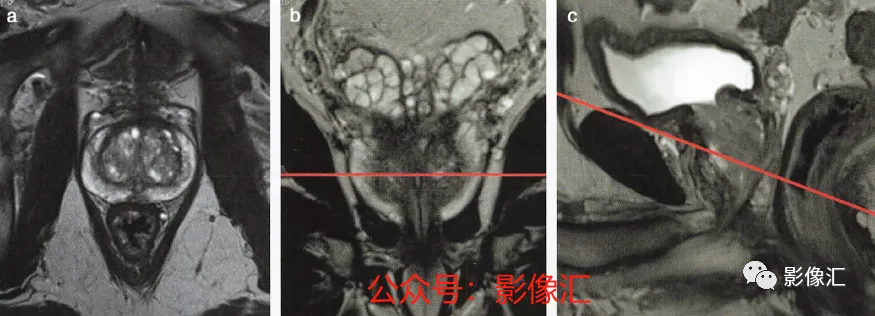

7. 前列腺下部水平的横轴面(图2.25)